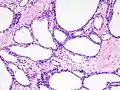

Micrografía mostrando un cistoadenoma seroso del páncreas. H&E stain.

Los patólogos clasifican las neoplasias quísticas serosas en dos grandes grupos. Aquellas que son benignas, que no se han diseminado a otros órganos, se denominan "cistoadenomas serosos".[4] Los cistoadenomas serosos pueden subdividirse en microquístico, oligocístico (o macrocístico), sólido, neoplasia endocrina mixta y neoplasia serosa asociada a VHL. Este último esquema de clasificación es útil porque destaca la variedad de aspectos y las asociaciones clínicas de estas neoplasias. Las neoplasias quísticas serosas que se han diseminado ("metastatizado") a otro órgano se consideran malignas y se denominan "cistoadenocarcinoma seroso".